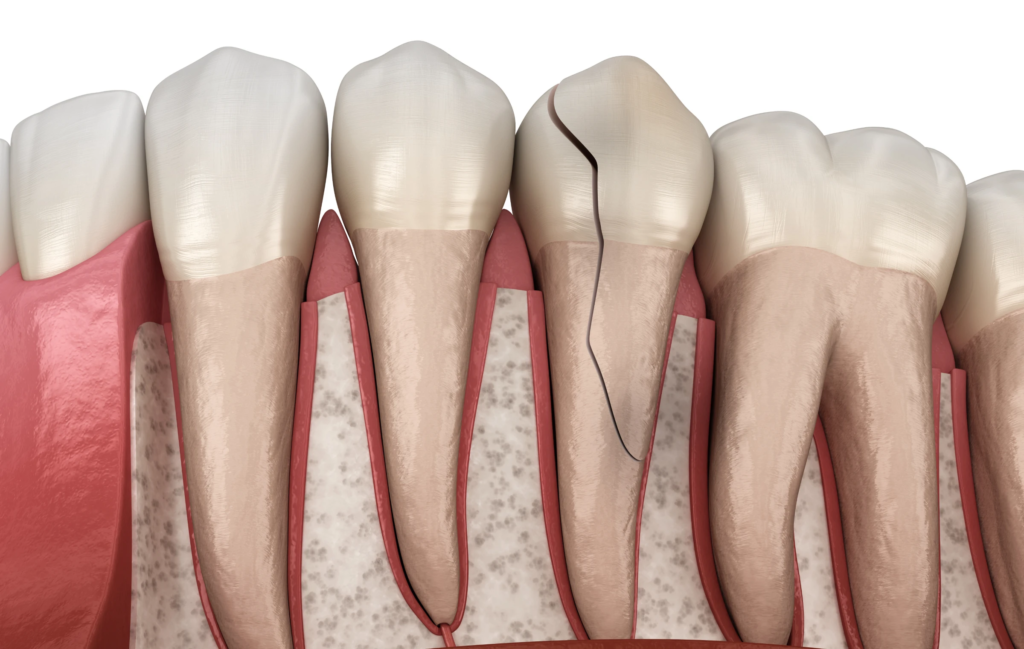

Les traumatismes dentaires se manifestent sous différentes formes : fissure, fracture, luxation (déplacement de la dent), expulsion complète ou lésion interne invisible à l’œil nu. Même une dent qui paraît intacte après un choc peut avoir subi un dommage au niveau de la pulpe (nerf et vaisseaux sanguins de la dent), justifiant un examen attentif par un chirurgien-dentiste.

La fêlure ou fracture de l’émail

Il s’agit du traumatisme dentaire le plus fréquent et le plus bénin. Dans ce cas, la dent présente simplement une petite cassure sans atteinte de la pulpe. En général, le traitement consiste à polir la surface pour éviter les irritations. Lorsque la fracture est visible, le praticien peut également reconstituer la dent avec un composite esthétique, afin de rétablir l’apparence naturelle du sourire.

La fracture coronaire avec atteinte de la dentine ou de la pulpe

Ce type de fracture est plus sévère, car il provoque souvent une douleur vive et peut exposer le nerf dentaire. Selon la gravité du cas, le chirurgien-dentiste peut restaurer la dent à l’aide d’un composite ou d’une couronne. Cependant, si la pulpe est atteinte, un traitement endodontique devient nécessaire afin de préserver la racine et d’éviter toute infection.

Ces fractures concernent la racine de la dent, une partie invisible à l’œil nu. Le traitement repose alors sur la stabilisation de la dent et un suivi radiographique régulier pour évaluer la cicatrisation. Dans certains cas, une intervention endodontique ou chirurgicale peut s’avérer nécessaire pour assurer la pérennité de la dent.